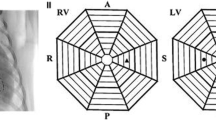

Multielectrode basket catheters were positioned endocardially in both ventricles for mapping and remained in the same position throughout the entire duration of all experiments (Fig. 1 A). These catheters were positioned as deep into the ventricles to permit contact along the complex intracavitary structures and its closely associated and overlapping His-Purkinje tissue. These regions that we refer to as the distal RV and LV are regions that we define as including the complex compartment of these ventricular regions including the RV moderator band, right- and left-sided papillary muscles, false tendons, and the distal Purkinje tissue. The locations of the mapping catheters were confirmed by fluoroscopy: a 38 mm Constellation catheter (Boston Scientific, Marlborough MA—64 electrodes on eight splines) was placed in the distal RV, a 60 mm Constellation catheter (Boston Scientific, Marlborough MA—64 electrodes on eight splines) was positioned in the distal LV, and an Orion catheter (Boston Scientific, Marlborough MA—64 electrodes on eight splines) was positioned in the RVOT (Fig. 1 C). A retrograde aortic approach was used to access the LV in all canines.

A and B Gross anatomy specimen of the canine heart showing placement of the multielectrode basket mapping catheters in the distal right ventricle (RV), the right ventricular outflow tract (RVOT), and the distal left ventricle (LV). Note the complex anatomy of these distal regions including the moderator band, false tendons, papillary muscle, and Purkinje tissue (labeled in the figure). C Fluoroscopic image (LAO view) illustrating the placement of the multielectrode basket mapping catheters. D Position of the multielectrode basket mapping catheters as displayed on the electroanatomical (EAM) map created using the Rhythmia EAM system